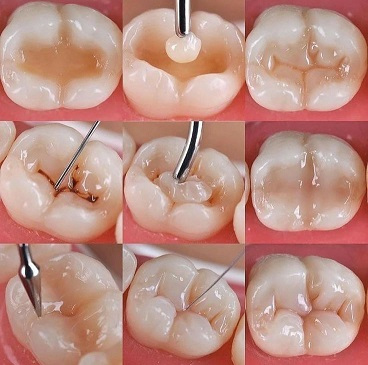

Фотополімерні пломби

Руставраційна стоматологія

Композити із якісних передових матеріалів. Комплексна реконструкція задніх та передніх зубів.